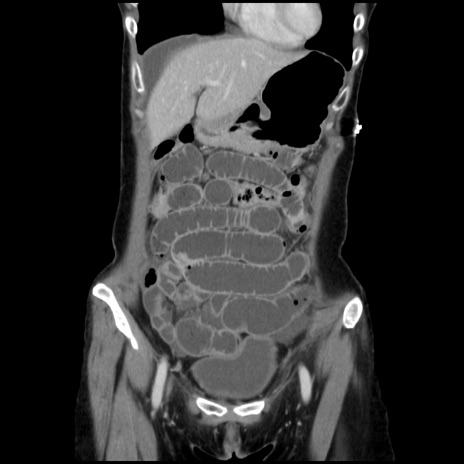

横断像

【症例】40歳代 女性

【主訴】上腹部痛、嘔気・嘔吐

【現病歴】約9時間前頃から急に上腹部痛、嘔気、嘔吐が出現。改善しないため救急要請。

【既往歴】子宮頚癌(広汎子宮全摘術、放射線療法)、腸閉塞

【身体所見】腹部:平坦、軟、腸雑音亢進、上腹部を中心に腹部全体に圧痛あり。

【データ】WBC 8400、CRP 0.03